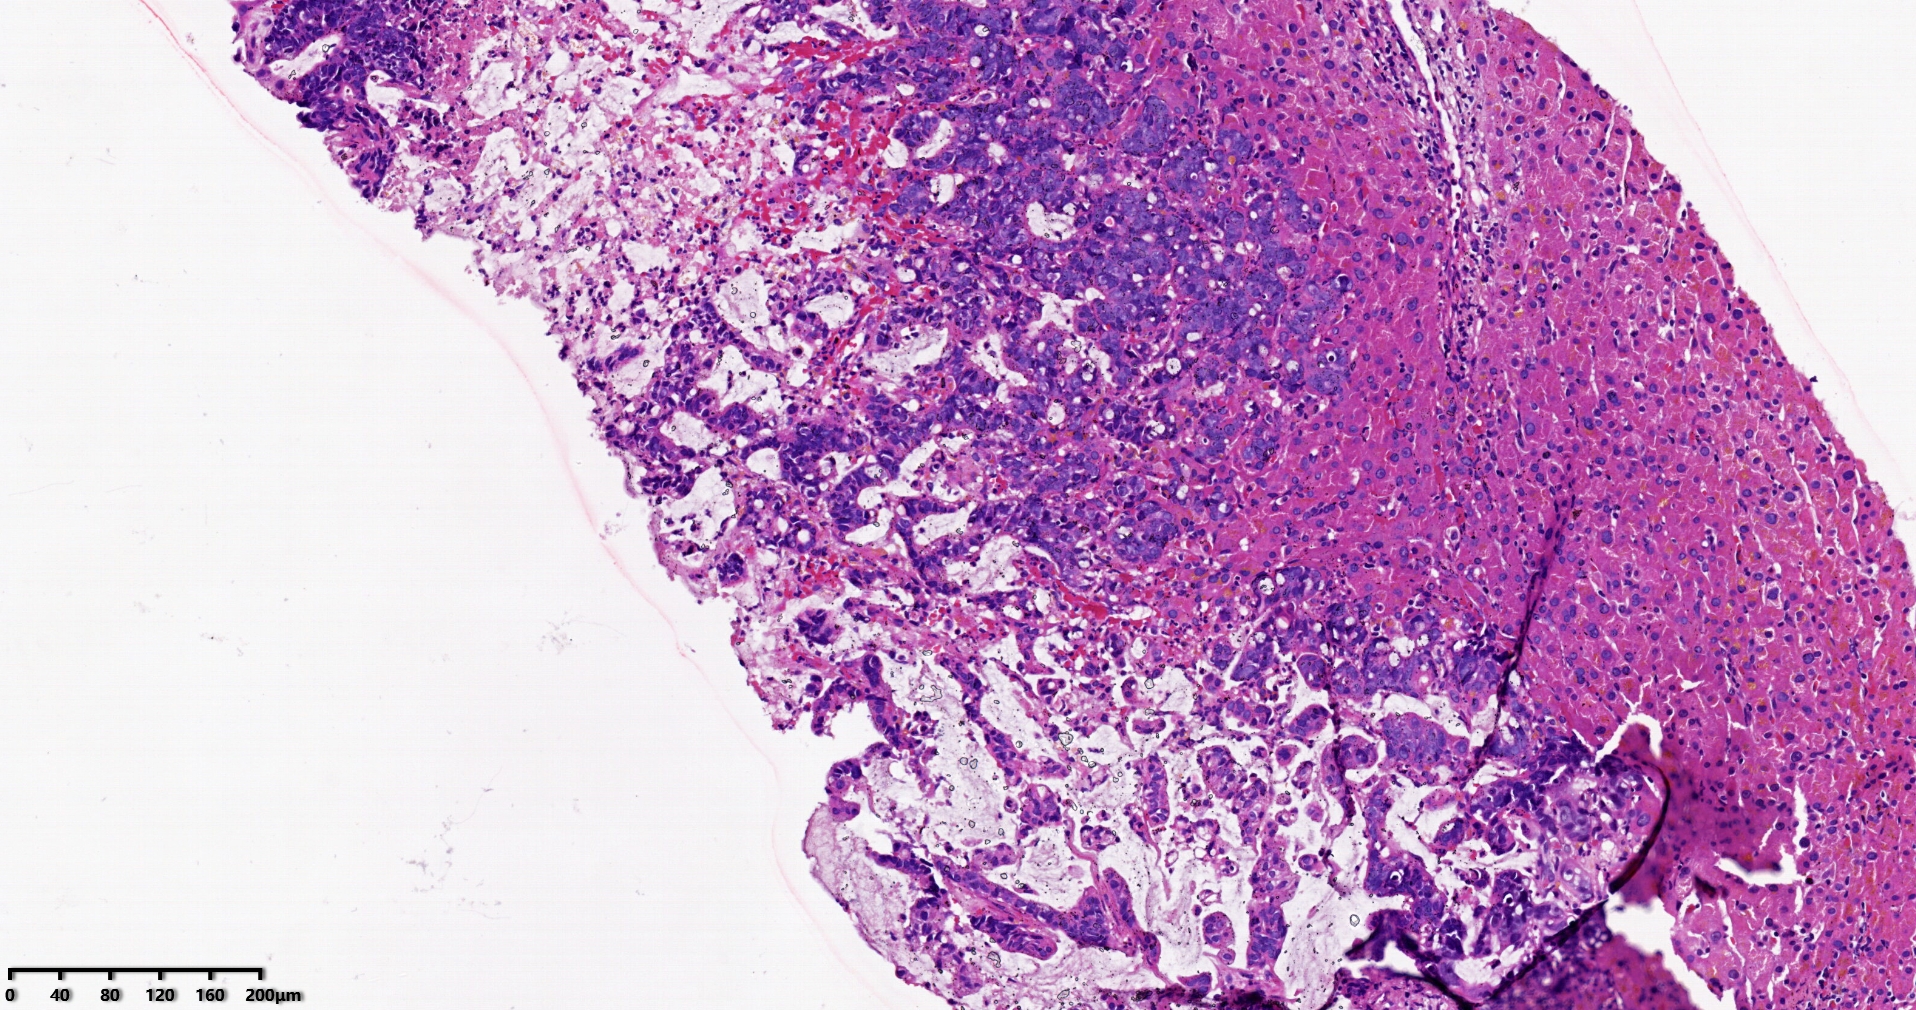

标本名称肝脏穿刺

大体所见灰白灰红色穿刺活检组织两条,长1.7-1.9cm,直径0.1-0.2cm。

考虑符合:肝内胆管癌

考虑转移性黏液腺癌,消化道来源可能,建议做免疫组化,排除胆管源性。